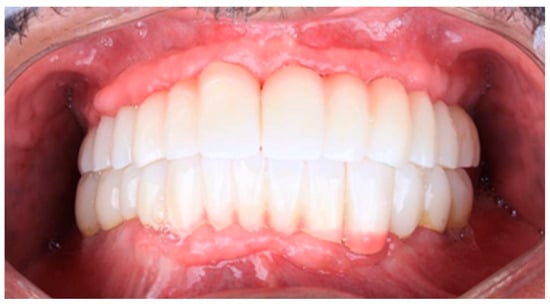

The restoration plan involved placing a bridge that connects the central incisors to the canines, along with an additional bridge spanning the first premolar to the first molar on each side of the maxillary arch. In the mandibular arch, the plan included three bridges: one connecting the lateral incisors bilaterally and another bridging the canines to the second premolars and first molars on each side (Figure 14 and Figure 15). Placing was confirmed using Panoramic radiographs obtained using the PantOs DG XP panoramic dental X-ray system (Fona S.r.l., Assago, Italy; CE 0051). The unit operates on a 230 V, 50/60 Hz input line with an 8 A fuse. Standard panoramic exposure parameters were applied (90 kVp, 10 mA, exposure time 14 s) following the manufacturer’s safety recommendations. A trained radiology technician performed all scans, and patient positioning was standardized using the built-in cephalostat support and light-beam alignment to ensure reproducibility of serial images.

Figure 14. The final prostheses.